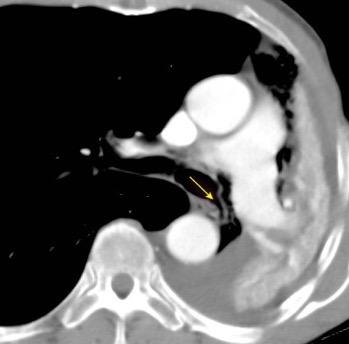

149. TORACOABDOMINAL: GANGLIOS

150. TORACOABDOMINAL: S SEUDOQUISTE PANCREÁTICO